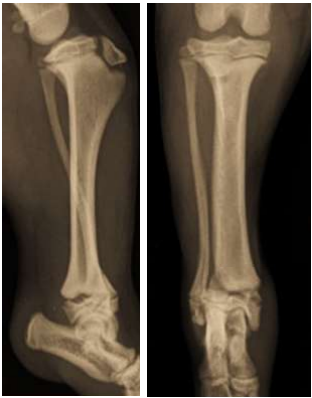

As radiografias abaixo pertencem a um Fox Terrier de 17 semanas de idade e evidenciam uma fratura distal da tíbia. Trata-se de uma fratura fechada, que se estende por três quartos da linha fisária tibial, prolongando-se até a metáfise lateral da tíbia:

Enunciado 4939636-1

A fratura não apresenta comunicação com a superfície articular. Com base nessa descrição, qual das seguintes opções melhor classifica essa fratura?